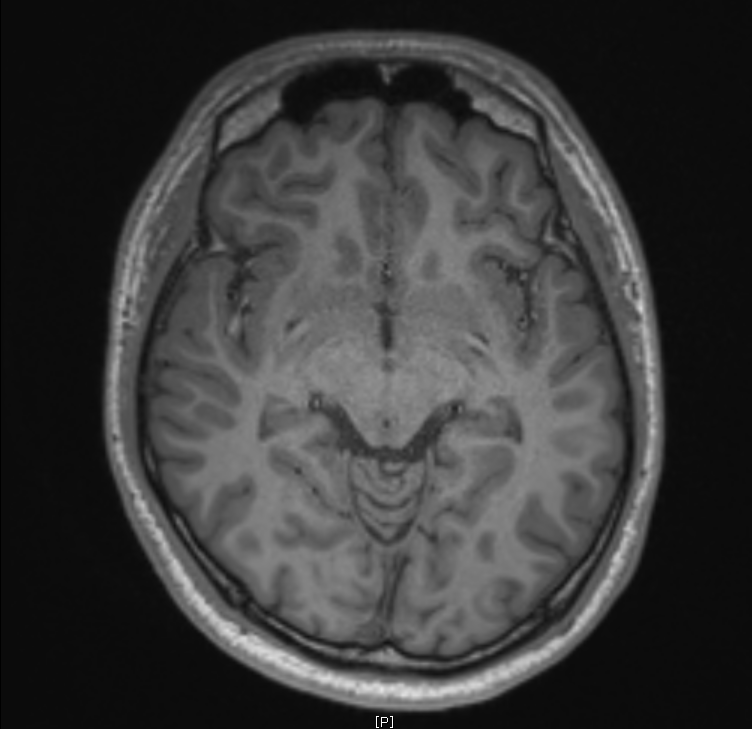

지난 금요일에 MRI를 촬영했는데요

혈관같기도 하고 하얀색 붕붕 뜨는 게 있어보이는데 (혈관같음)

한번 봐주실수 있나요? 그리고 전체적으로 괜찮은지도 봐주시면 감사하겠습니다.

특별하게 눈에 띄는 병변은 있어보이지 않습니다

말씀하신 것은 혈관의 가능성이 높겠습니다